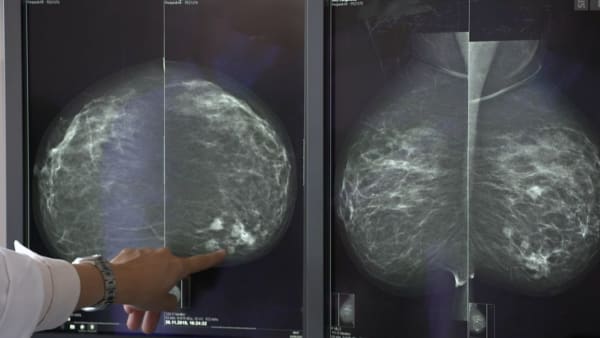

Die Überlebenschancen von Krebspatienten stehen besser, wenn sie in zertifizierten Zentren behandelt werden. Ihre Sterblichkeitsrate lag bei acht untersuchten Krebserkrankungen niedriger als bei denjenigen, die in nicht zertifizierten Kliniken behandelt wurden.

Zu diesem Schluss kommt eine deutsche Studie. Diese basiert auf bundesweiten Abrechnungsdaten der Allgemeinen Ortskrankenkasse (AOK) sowie auf Daten aus vier regionalen Krebsregistern. Rund eine Million Behandlungsfälle wurden ausgewertet. Die Studie lief über einen Beobachtungszeitraum von acht Jahren (2009 bis 2017).

Bei Patienten, die sich in einem zertifizierten Zentrum behandeln liessen, war der Überlebensvorteil bei folgenden Krebsarten besonders gross:

> Gebärmutterhalskrebs (fast 26 Prozent weniger Sterblichkeit)

> Neuroonkologische Tumore (15,8 Prozent weniger Sterblichkeit)

> Lungenkrebs (15 Prozent weniger Sterblichkeit)

> Brustkrebs (11,7 Prozent weniger Sterblichkeit)

Die niedrigere Sterblichkeit in den zertifizierten Zentren war sowohl in den Krebsregister-Daten als auch in den Krankenkassendaten erkennbar. Die Ergebnisse stützten über verschiedene Krebsarten hinweg die Hypothese, dass Patienten in zertifizierten Kliniken bessere Überlebenschancen hätten als in nicht zertifizierten Krankenhäusern, sagte einer der Studienautoren.

Gemäss der Analyse haben Patienten mit den niedrigeren Tumorstadien I bis III stärker von der Zentrumsbehandlung profitiert als Patienten mit dem fortgeschrittenen Stadium IV. Wie eine Autorin der Studie erklärt, «dürfte zum Beispiel der Einsatz von Tumorboards, die das diagnostische und therapeutische Vorgehen bei Patienten mit malignen Tumoren gemeinsam besprechen und die weitere Behandlung planen, eine grosse Rolle für den Erfolg der zertifizierten Zentren gespielt haben».